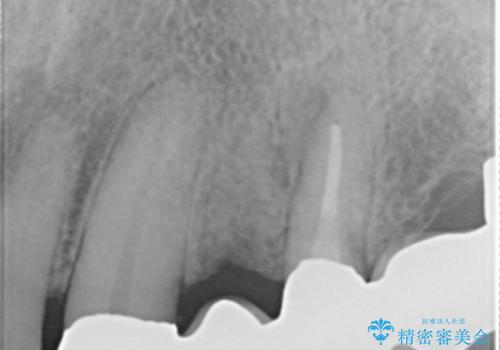

精査したところ、歯ぐきが腫れている左上の小臼歯(左上4)は保存不可能な状態でした。

保存不可能な歯(左上4)を抜去後、ブリッジによる補綴治療を行いました。

- ¥760,000 (根管治療×2本、土台×2本、仮歯×5本、クラウン×5本)費用は治療当時の料金となります